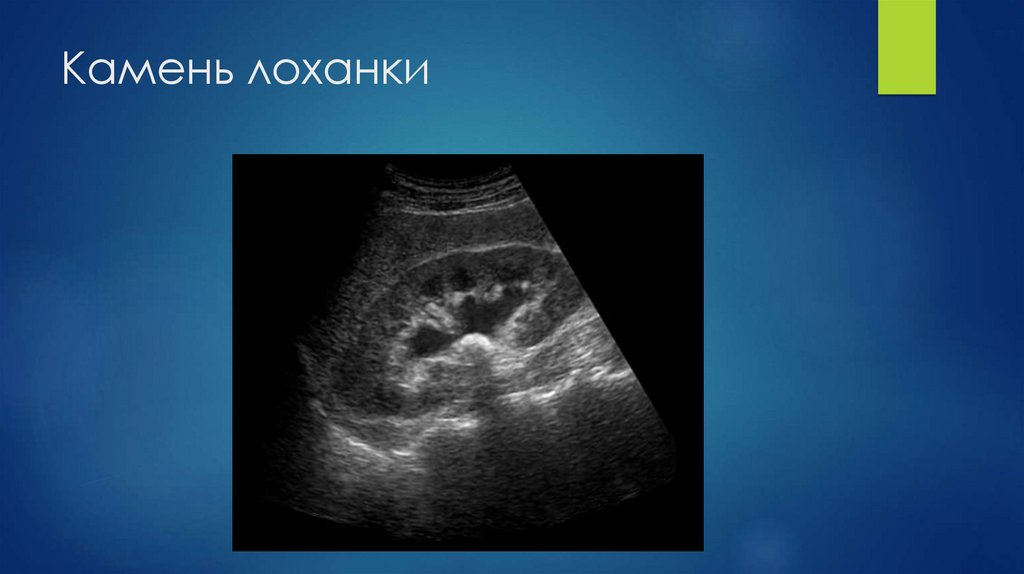

15. Камень лоханки